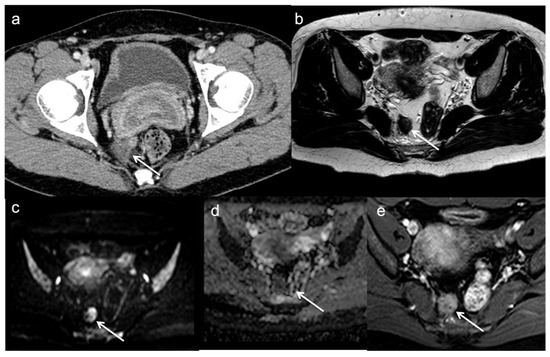

- Lambregts, D.M.; Lahaye, M.J.; Heijnen, L.A.; Martens, M.H.; Maas, M.; Beets, G.L.; Beets-Tan, R.G. MRI and diffusion-weighted MRI to diagnose a local tumour regrowth during long-term follow-up of rectal cancer patients treated with organ preservation after chemoradiotherapy. Eur. Radiol. 2016, 26, 2118–2125. [Google Scholar] [CrossRef]

- Sinaei, M.; Swallow, C.; Milot, L.; Moghaddam, P.A.; Smith, A.; Atri, M. Patterns and Signal Intensity Characteristics of Pelvic Recurrence of Rectal Cancer at MR Imaging. Radiographics 2013, 33, E171–E187. [Google Scholar] [CrossRef]

- Dresen, R.C.; Kusters, M.; Daniels-Gooszen, A.W.; Cappendijk, V.C.; Nieuwenhuijzen, G.A.P.; Kessels, A.G.H.; Kessels, A.G.H.; de Bruïne, A.P.; Beets, G.L.; Rutten, H.J.T.; et al. Absence of tumor invasion into pelvic structures in locally recurrent rectal cancer: Prediction with preoperative MR imaging. Radiology 2010, 256, 143–150. [Google Scholar] [CrossRef]